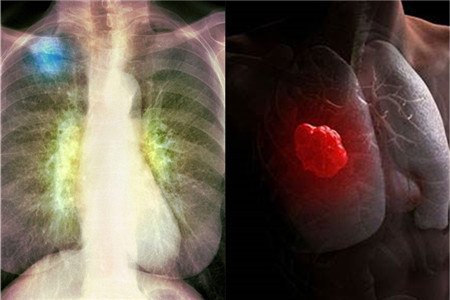

我们生活在当下时代,不得不说是幸运与不幸的结合。之所以幸运是因为经济快速发展,人们已经摆脱了基本的物质生活需求。不幸是因为环境遭到了破坏,长期生活在劣质环境中,难免会患上肺癌等各种病症。那么,怎样预防肺癌发生呢?